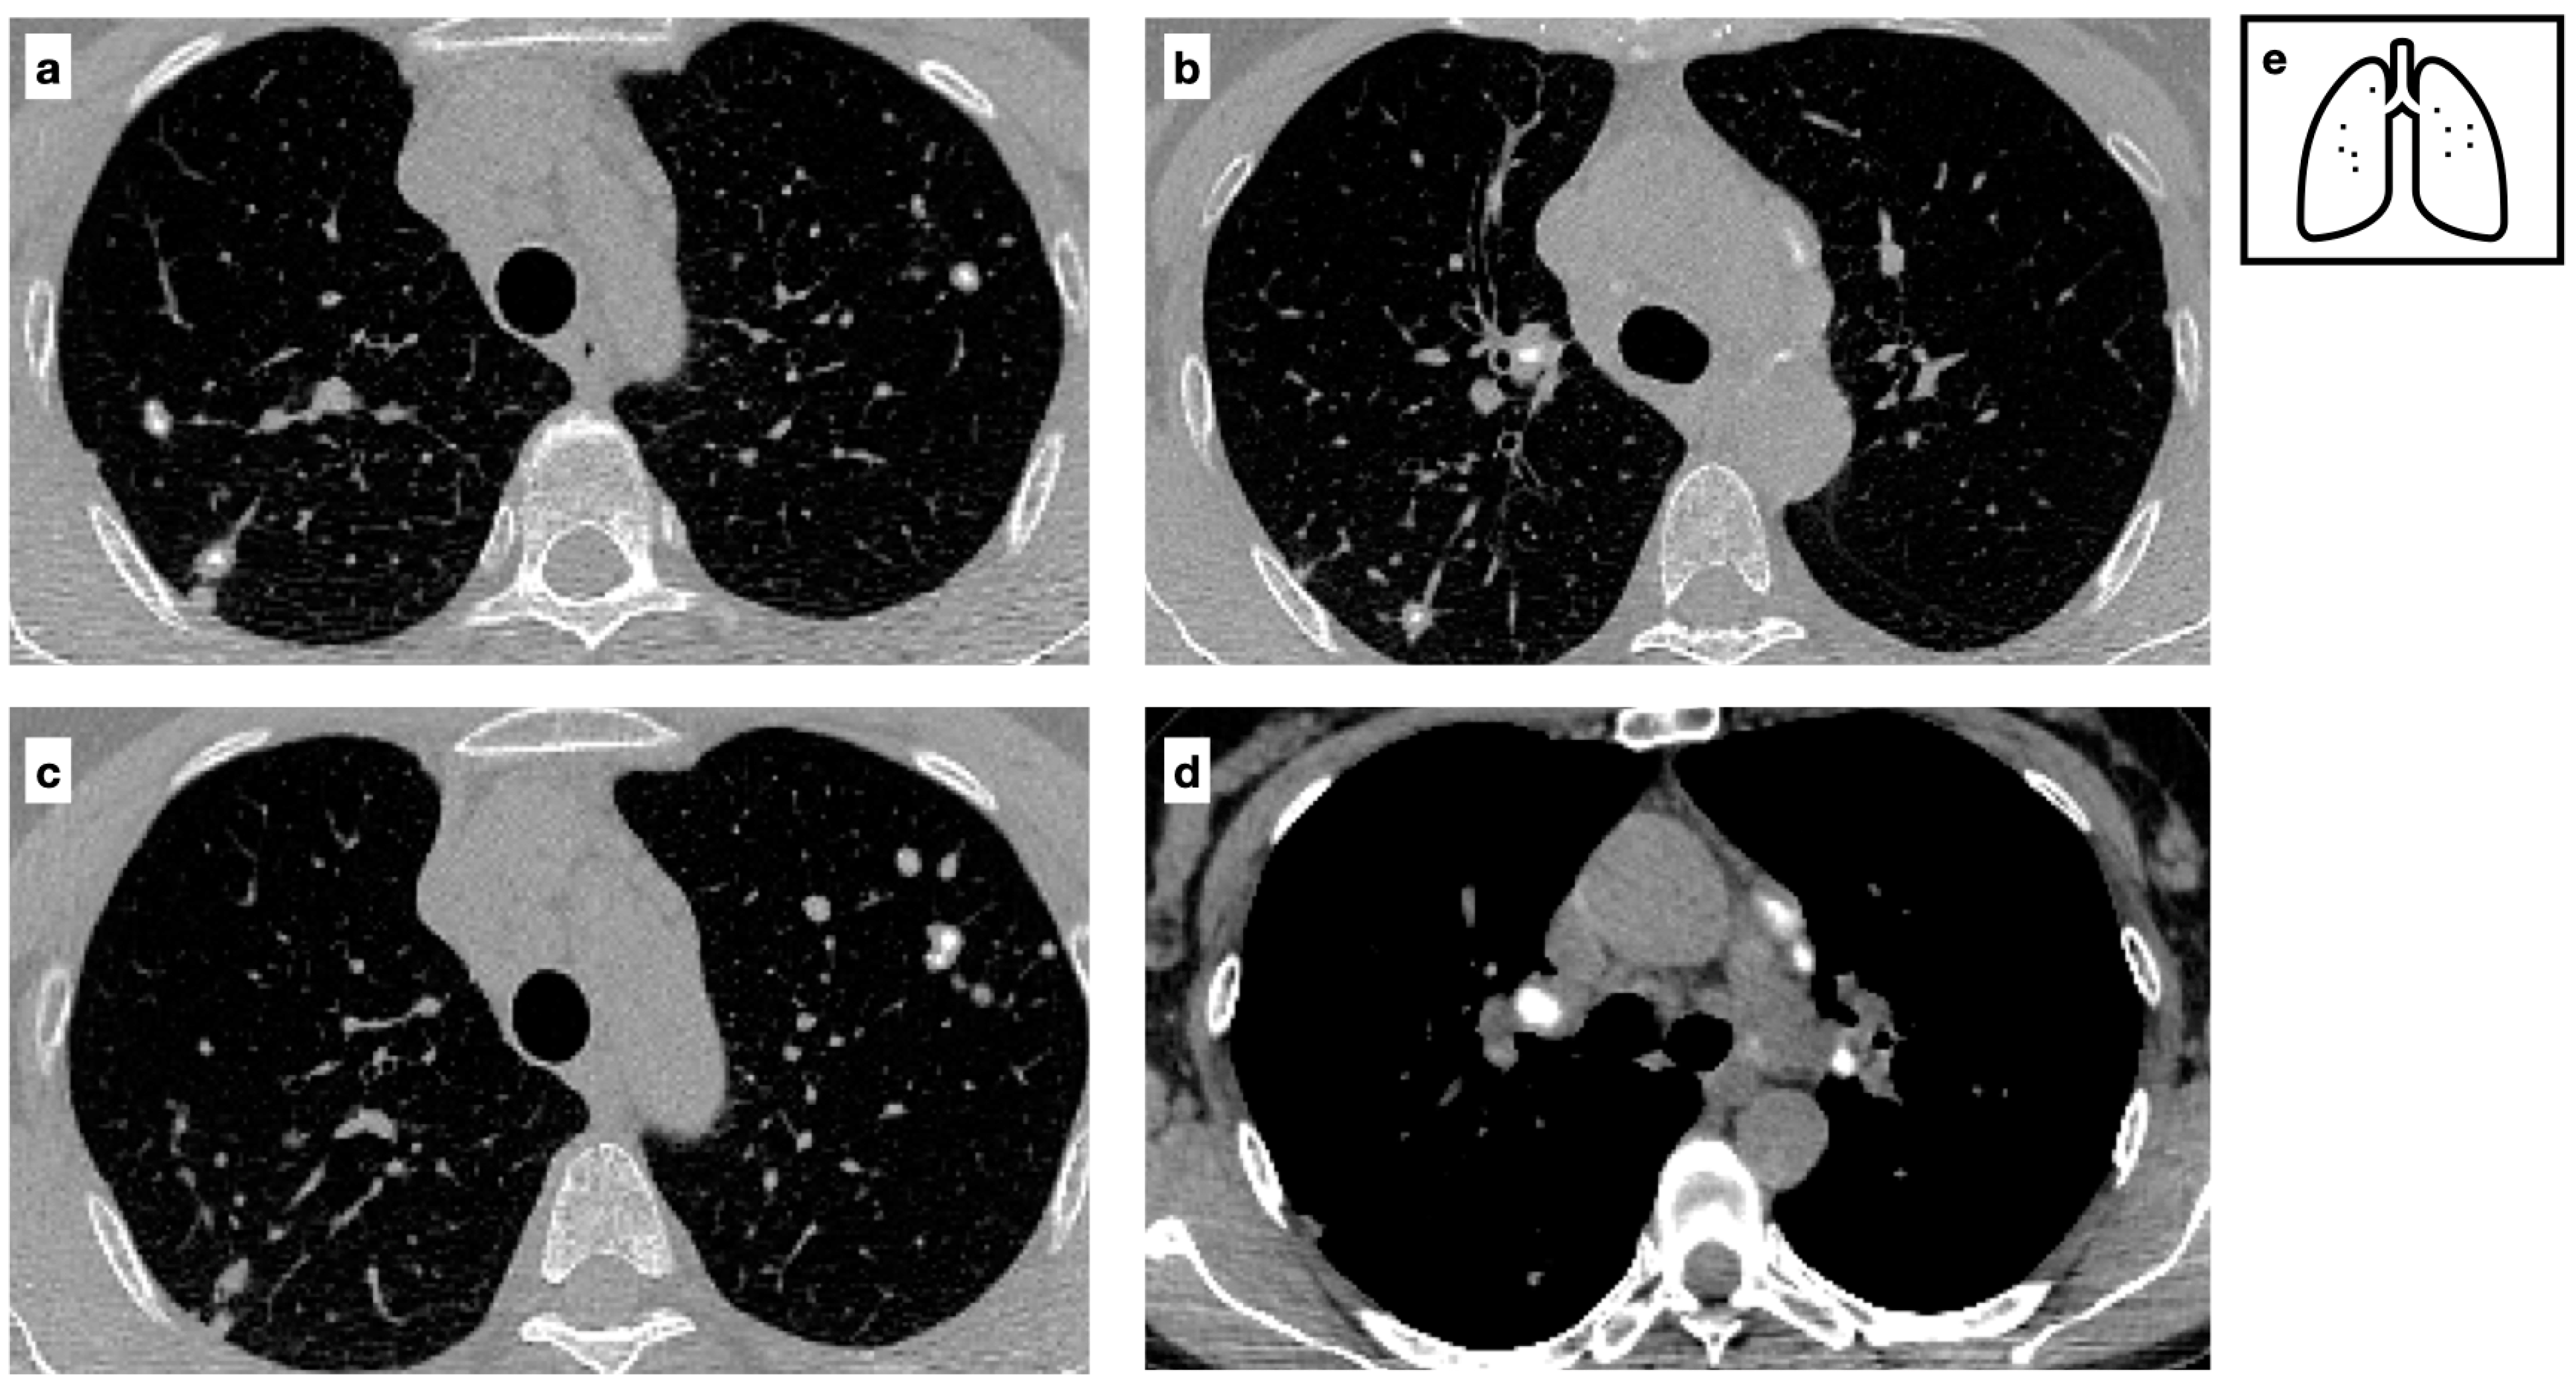

Figure 6.

CT scans of a Patient with a diagnosis of sarcoidosis demonstrating multifocal nodules characterized by central calcifications (a–c) and calcified lymph nodes are present within the mediastinum (d). Mediastinal lymphadenopathy in sarcoidosis is typically bilateral and symmetric; lymph nodes may calcify over time, commonly exhibiting ‘popcorn’, amorphous and punctate calcifications. Pattern of calcification (e).